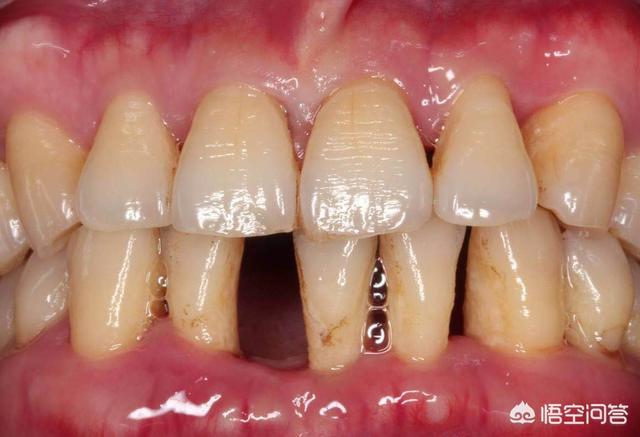

2.歯周炎による歯のゆるみ

歯周炎によって引き起こされるいくつかの理由による場合は、歯周組織に影響を与えるだけでなく、長期的な歯周炎はまた、歯周膜繊維が直接歯周組織を攻撃し、細菌の様々な口腔が損傷を受け、歯周炎が順番に悪循環を形成し、歯茎の後退を悪化させるだけでなく、歯茎を破壊するだけでなく、歯のゆるみにつながった歯の硬さに影響を与えます。

さらに、歯周組織が退行性変化を起こすと、歯周線維の破壊や歯槽骨の吸収が起こりやすくなり、歯のゆるみにつながる。

臨床症状:歯のゆるみに加えて、歯肉のうっ血、発赤、腫脹、歯周ポケットの形成、ひどい場合には膿瘍の形成を伴うことがある。

治療:ゆるみが2mm以下であれば、歯肉縁上清掃や歯肉縁下掻把、咬合調整、食物挟み込みの除去、抗生物質の使用、膿瘍の切開排膿などを行うが、ゆるみが2mm以上であれば抜歯をお勧めする。

歯周炎患者は、歯周支持組織の喪失と歯根を包む歯槽骨の吸収により、さまざまな程度の歯のゆるみを経験し、歯槽骨の吸収が重度の場合は歯を失う可能性がある。

歯周炎で歯が抜けた場合、歯石がたくさん付着していたり、歯肉の退縮で黒い三角形が現れたり、歯肉から出血したりすることで現れます。歯周病治療を行うには、最も基本的な方法は、超音波洗浄、歯肉縁下スクレイピングで歯の周りの歯石や歯垢など炎症の原因となるものを取り除くことです。また、歯のセルフクリーニングを入念に行う(歯磨きのたびに必ずフロスを使用する)ほか、定期的な検診を受け、病変の後退が遅れている場合は、状況に応じて歯周外科治療を受けることになりますが、この治療の主な目的は、歯の周囲の炎症を完全に除去し、治癒を促進することです。